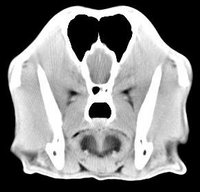

imágenes de TC en el perro | ||||||||||

ejemplo de imágenes de TC en el perro. Nótese la celulitis en la región parotídea izquierda | ||||||||||